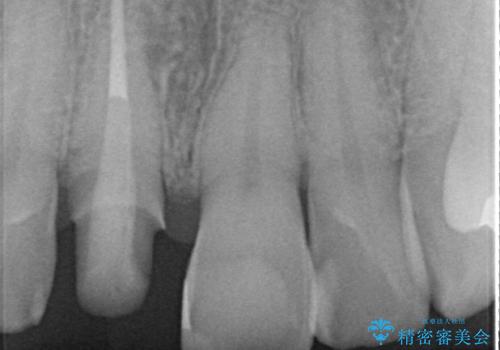

- 前歯の変色が気になり審美障害の改善を求めて来院されました。

根管治療に伴う歯の色調変化はよく見られる所見です。

セラミッククラウン製作を行い審美性の改善を計画します。